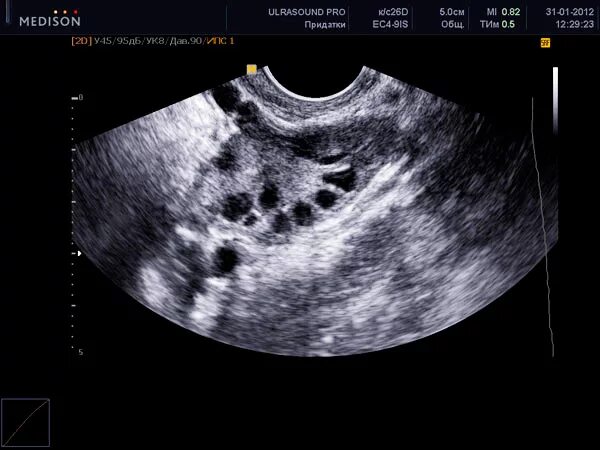

Когда делать узи яичников